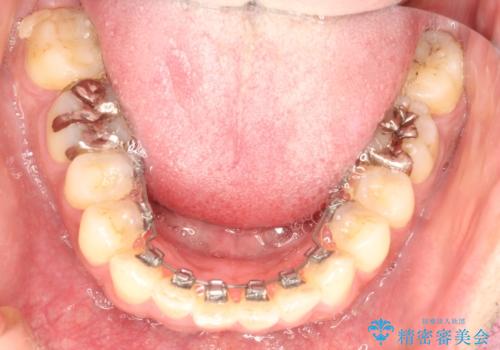

目立たない装置がご希望でしたので、上下裏側ワイヤー装置を選択されました。

裏側矯正は目立たないという利点がありますが、歯ブラシが非常に難しいなどのデメリットもあります。

- 治療中は歯磨きがしにくくなるため、虫歯や歯周病になりやすくなります